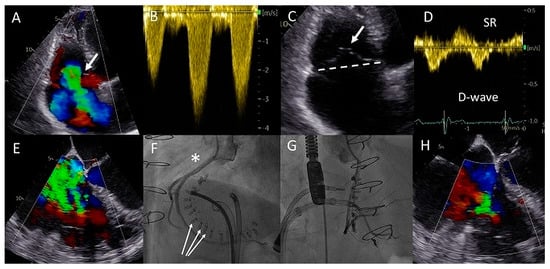

Figure 3.

(A) Color Doppler apical four-chamber view shows torrential tricuspid regurgitation (TR) with a wide vena contracta (arrow) and flow disturbance filling the enlarged right atrium. (B) Continuous wave doppler showing a dense TR signal with elevated right ventricular pressures. (C) Noncoaptation of the tricuspid valve (TV) leaflets (arrow) and annulus dilatation (dash line, 53 mm) is seen. (D) The hepatic vein Doppler demonstrates a pattern in atrial fibrillation with a prominent and late peaking systolic reversal (SR) wave. The only forward flow is evident in diastole (D-wave). (E) Two TR jets (a vena contracta of 4 and 7 mm, respectively, ERO of 90 mm2, regurgitant volume of 98 mL) are evident during transesophageal imaging. (F) Left anterior oblique and (G) right superior oblique fluoroscopic views showing patent right coronary artery (asterisk) and 18 anchors (arrows) between the two TV commissures allowing the Cardioband to significantly reduce the annulus dimensions. (H) Transesophageal echocardiography showing significant reduction in TR after the Cardioband annulus reduction procedure (appreciate the difference with panel (E), vena contracta of 3 and 5 mm, respectively, ERO 35 mm2, regurgitant volume of 41 mL).

The patient underwent a successful Cardioband annular reduction using right venous femoral access under general anesthesia with fluoroscopic (selective cannulation of the right coronary artery) and TEE guidance (Figure 3E–H). A total of 18 anchors were placed between the anteroseptal and posteroseptal commissure reducing the annulus dimensions to 45 × 36 mm. The torrential TR (two jets) was reduced to moderate TR (Figure 3E,H). At two years follow-up, the patient was in NYHA functional class I-II and no heart-failure-related admissions occurred. His NT-proBNP serum levels decreased to 2762 ng/L and at echocardiography he had a stable moderately reduced RV function and moderate TR.